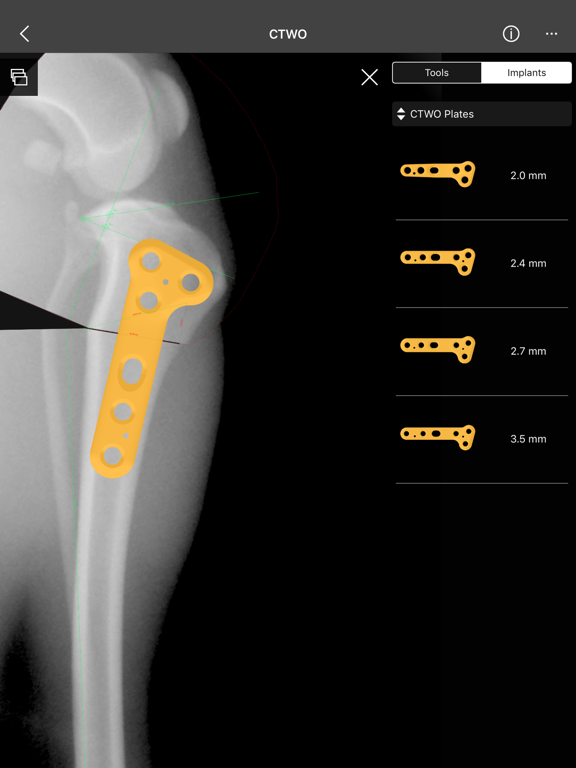

4. Catalogue of BETA Implants locking plates, in 2.0, 2.4, 2.7 and 3.5 sizes:

l) CTWO plates